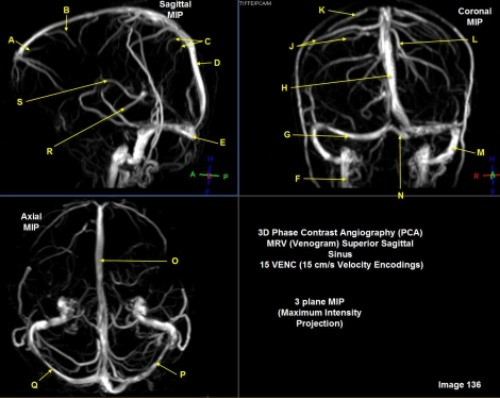

Letter C in Image 136 is pointing to:

E. Vein of trolard

C. Parietal veins

Letter Q in Image 136 is pointing to:

F. Left sigmoid sinus

A. Right transverse sinus

Letter F in Image 136 is pointing to:

E. Internal cerebral vein

D. Internal jugular vein

Letter D in Image 136 is pointing to:

D. Superior sagittal sinus

Letter J in Image 136 is pointing to:

C. Right parietal veins

Letter M in Image 136 is pointing to:

Letter R in Image 136 is pointing to:

F. A and / or C

Letter P in Image 136 is pointing to:

B. Left transverse sinus

Letter G in Image 136 is pointing to:

E. Left transverse sinus

D. Right transverse sinus

Letter K in Image 136 is pointing to:

Letter E in Image 136 is pointing to:

E. Posterior sigmoid sinus

C. Torcular herophili

Letter B in Image 136 is pointing to:

B. Posterior frontal vein